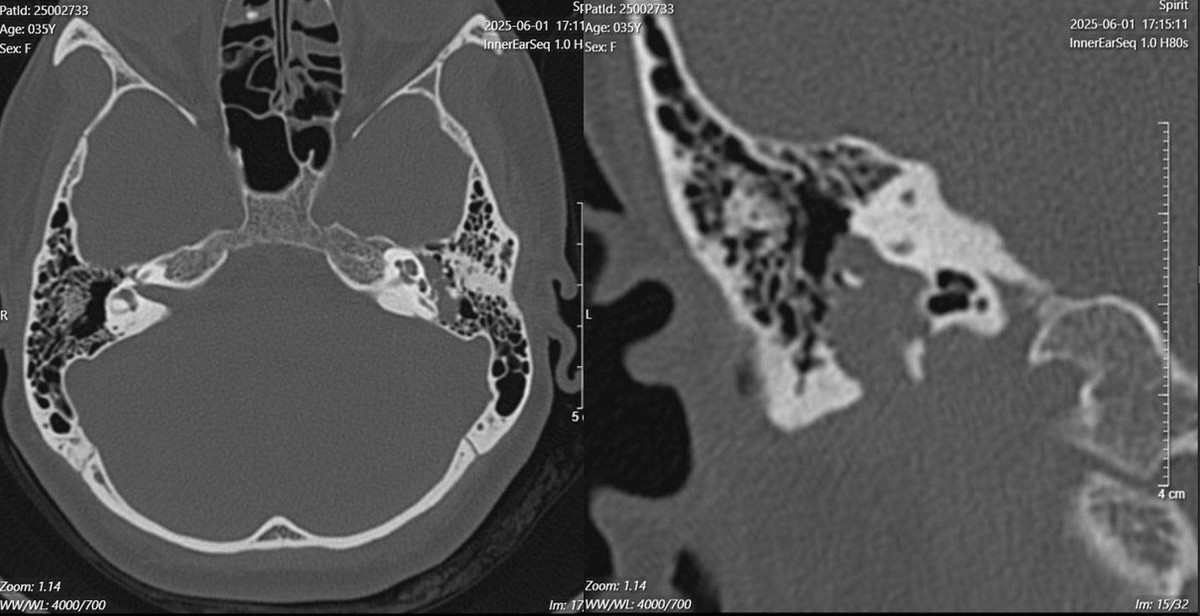

Tại đây, các bác sĩ đã tiến hành nội soi tai, phát hiện khối màu hồng ở phía sau màng nhĩ. Hình ảnh trên cắt lớp vi tính và cộng hưởng từ (MRI) cho thấy một khối u lớn ở đoạn II và III dây thần kinh mặt – nguyên nhân gây liệt mặt kéo dài suốt nhiều năm.

Sau khi hội chẩn liên chuyên khoa, chị T. được chẩn đoán liệt mặt hoàn toàn bên trái do khối u thần kinh mặt bên trái và có chỉ định phẫu thuật mở xương chũm lấy toàn bộ khối u đồng thời thực hiện kỹ thuật nối dây VII – XII để phục hồi chức năng vận động cơ mặt.

Hình ảnh phim chụp cắt lớp vi tính cho thấy khối mờ nằm dọc theo đoạn II và đoạn III của dây thần kinh mặt trong xương chũm - Ảnh BVCC